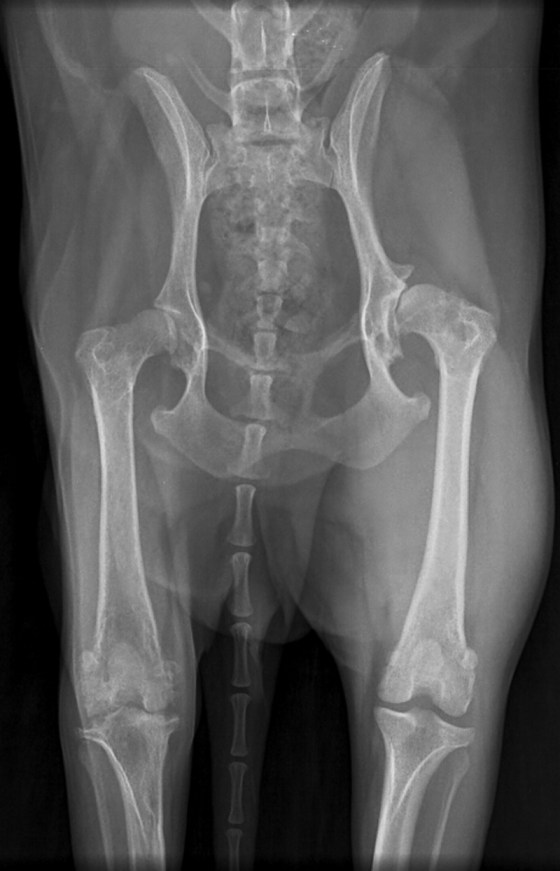

Signalement: femelle Shih Tzu stérilisée de 7 ans.

Histoire clinique: boiterie progressive au membre pelvien droit. Radiographie effectuée pour suspicion d’atteinte aux hanches.